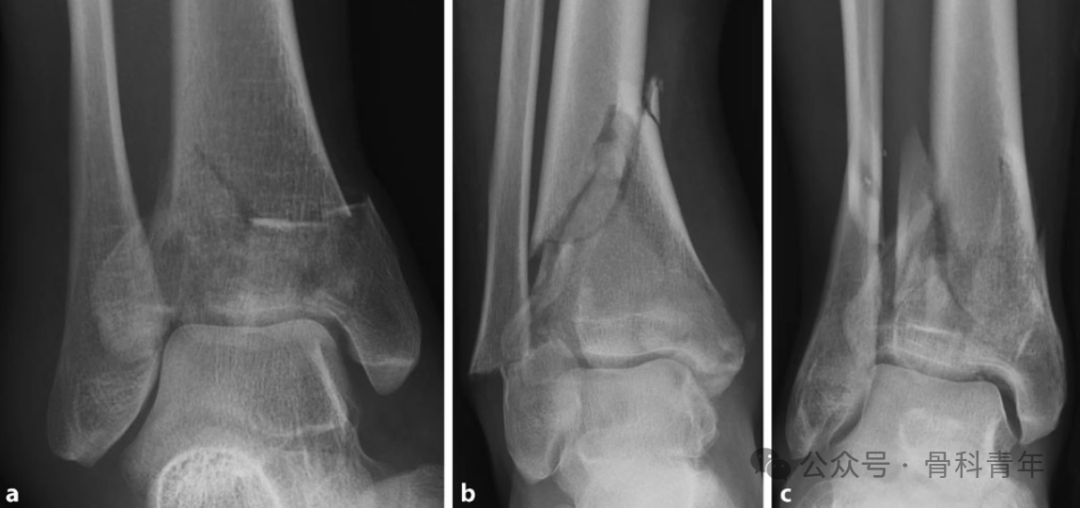

腓骨完整时,胫骨承受轴向压力而发生的骨折(a); -

胫骨内翻畸形,外侧受牵拉力,内侧受压力(b); -

胫骨外翻畸形,外侧受压力(c);